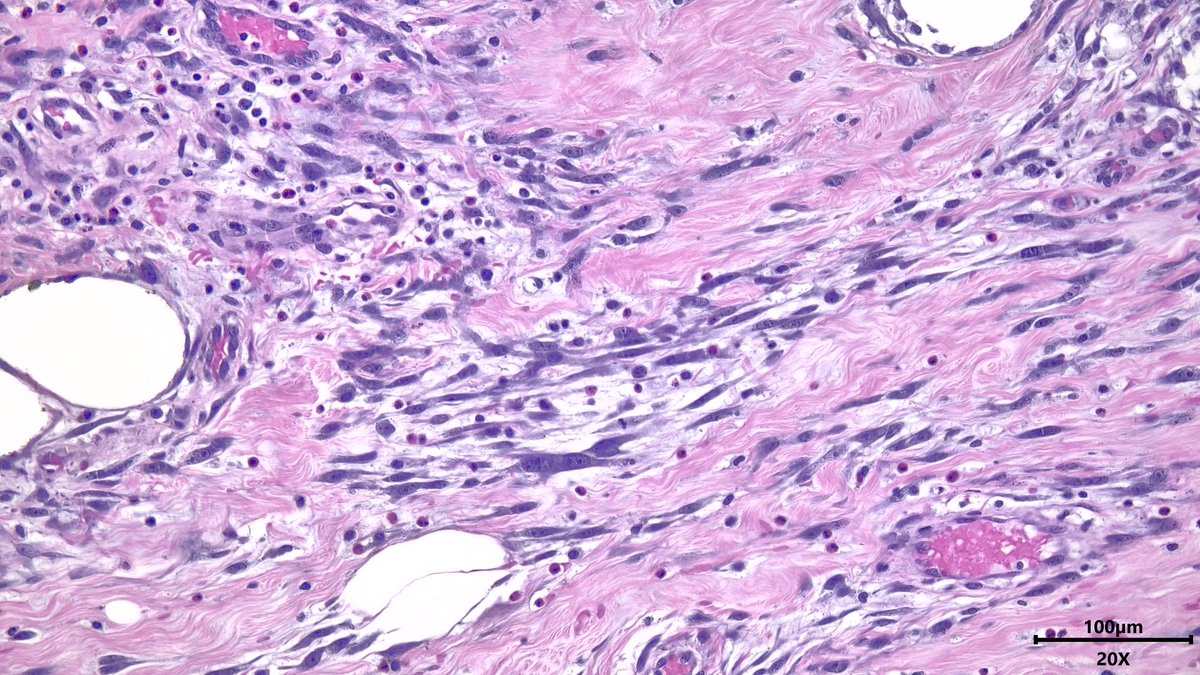

67 male with soft tissue masses, including paratesticular (1 & 2) and spleen (3) It looks like Liposarcoma but actually he had Primary Myelofibrosis for a while IHC is CD61 This is a Sclerosing extramedullay hematopoietic tumor, rare complication of Myeloproliferative neoplasms